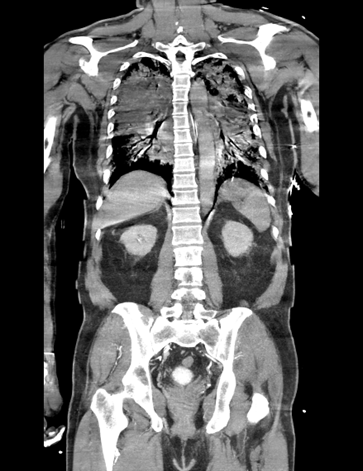

Relevant Test Results Prior to Catheterization

ECG showed sinus rhythm with ST-segment elevation in V1–V3 and aVL, consistent with anterior STEMI. Brain CT excluded intracranial hemorrhage. Chest CT ruled out aortic pathology but revealed diffuse ground-glass opacities suggesting pulmonary edema. Echocardiography showed severe LV dysfunction with EF 18% and diffuse hypokinesis. Cardiac enzymes were markedly elevated.